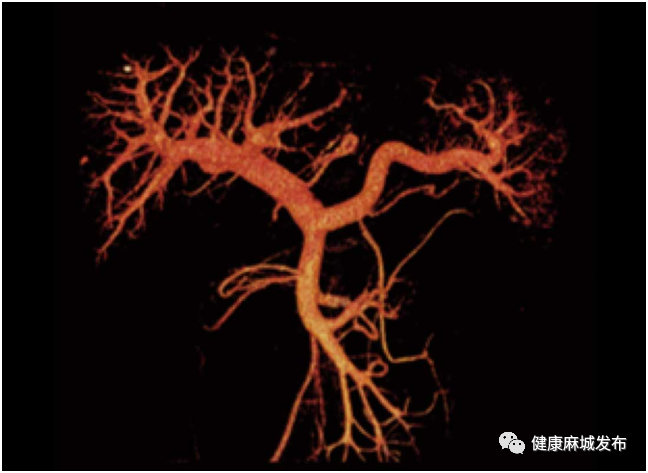

智能一键去骨:针对头颈部、体部、四肢以及泌尿系统各自具备不同解析算法,实现不同部位的精准去骨,助力医生精准诊断。